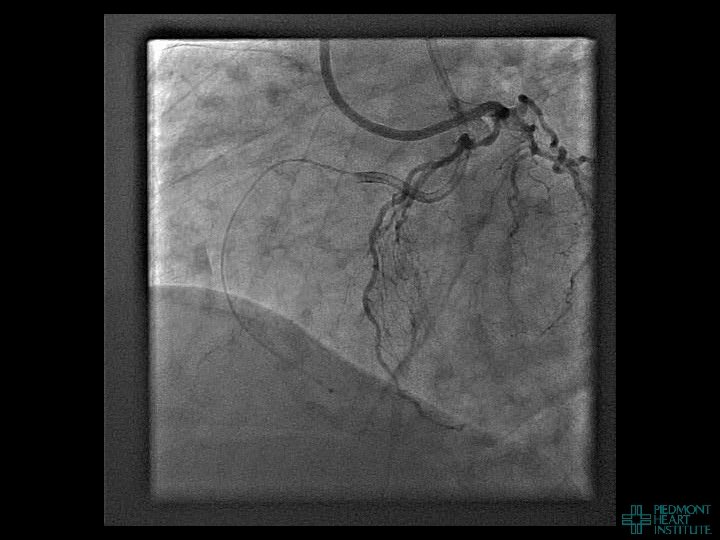

Case Example 3